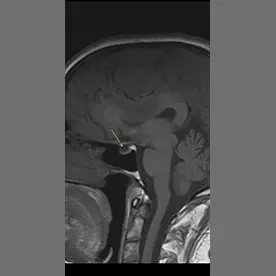

Es zeigt sich eine ausgedehnte Raumforderung des Kleinhirnbrückenwinkels rechts mit einem sogenannten "dural tail sign" (Bild 10-1, Pfeil). Die Raumforderung zeigt ein Wachstum nach intrameatal rechts (Bild 10-2, Pfeil) und entlang des Foramen ovale (Bild 10-3, Pfeil). Es zeigt sich ein ausgeprägtes verdrängendes Wachstum ohne Perifokalödem (Bild 10-4). Insgesamt passt dieses Bild zu einem Meningiom.

Typisches Bild eines Meningioms